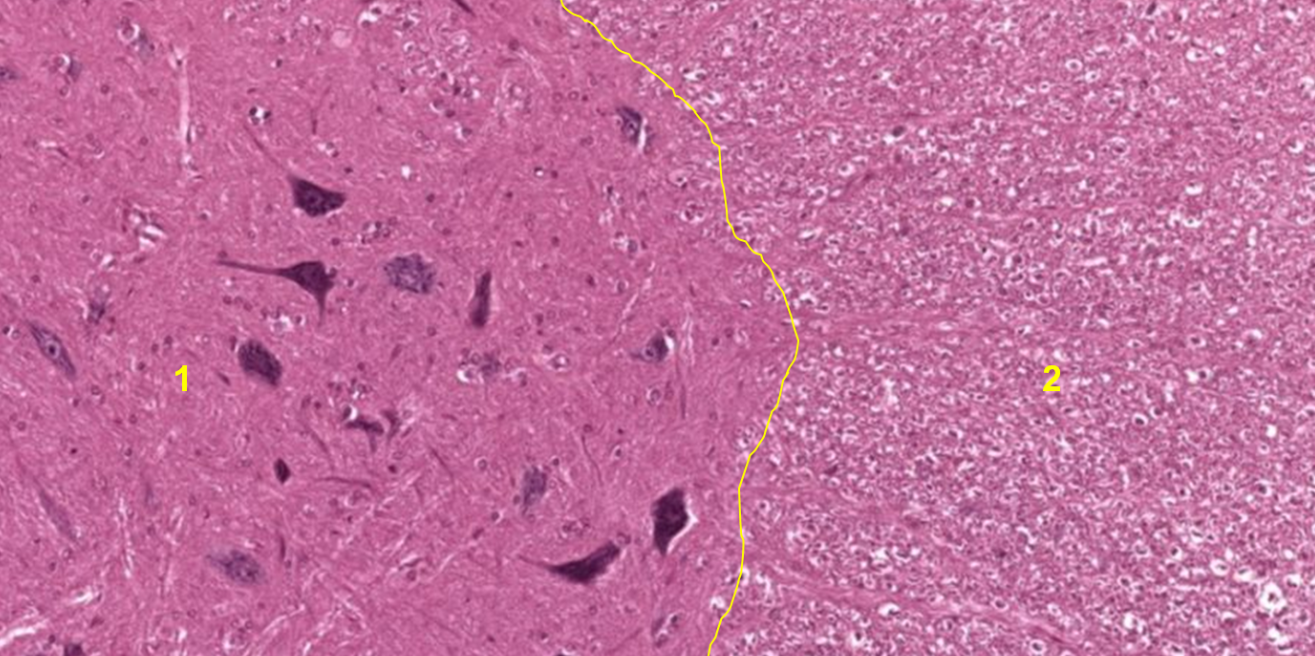

Medula espinhal (1: substância cinzenta; 2: substância branca)

Medula espinhal